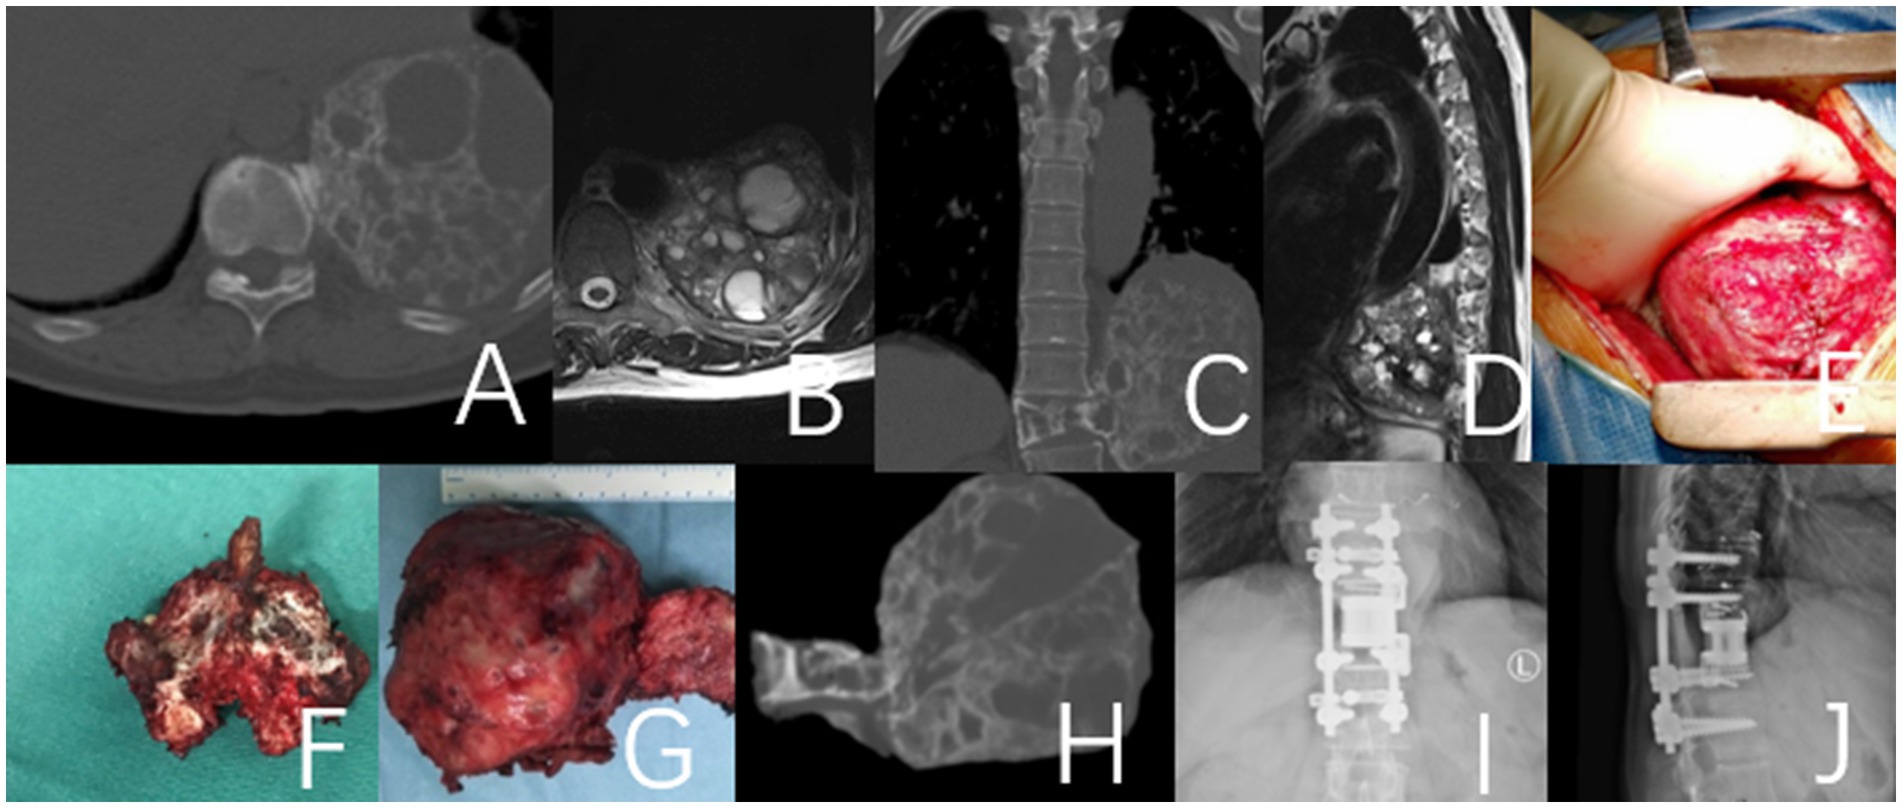

Figure 1. This case involves a 50-year-old female patient with a T11 giant cell tumor, classified under the WBB staging system as T11 1–10 (A–D). The patient received denosumab treatment for 3 months prior to undergoing staged T11 en bloc resection surgery, during which a 3D-printed artificial vertebra was implanted between T10 and T12, and subsequently fixed. During the surgery, tumor operations were executed while cutting both sides of the pedicles. During posterior approach surgery, a tear in the right pleura resulted in pleural effusion, which was resolved with adequate drainage, leading to a full recovery. (A–D) Preoperative CT and MRI images revealed a large mass in the thoracic cavity formed by the T11 vertebral tumor. (E) Second-phase anterolateral approach surgery. (G) Specimen of the second phase surgery. (F) Specimen of the first phase posterior surgery. (H) CT images of the T11 vertebra and tumor excised during the second-stage surgery. (I,J) Imaging at the 4-year postoperative follow-up indicated that the internal fixation was well positioned and showed no evidence of tumor recurrence.